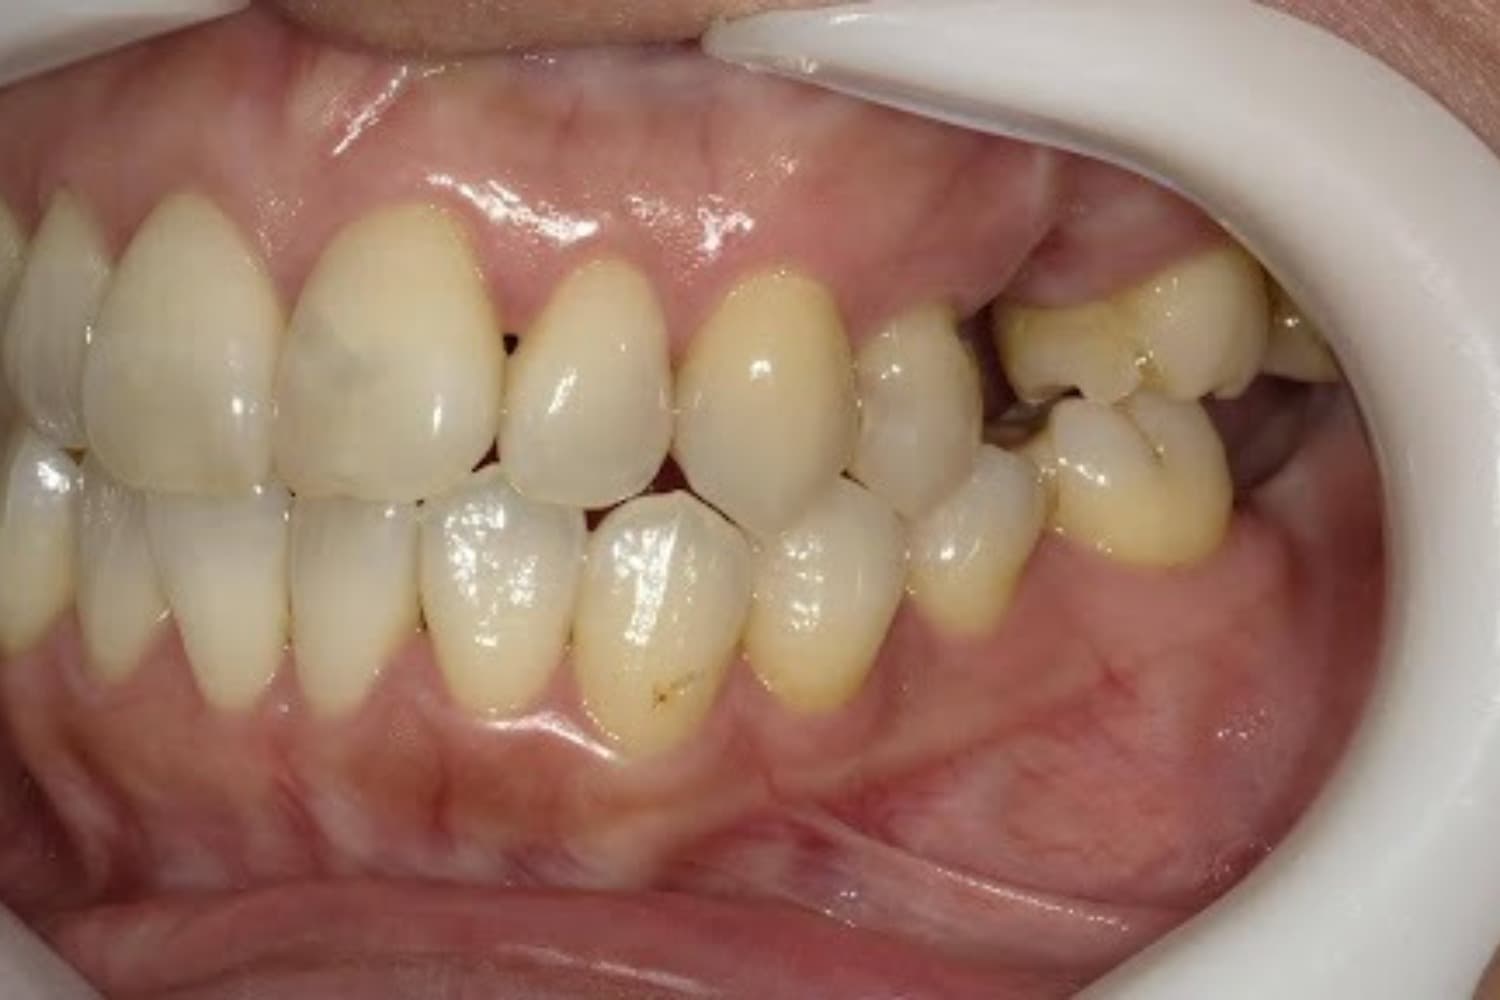

右上の歯のインプラント治療(50代女性)

Before

After

グラフトレスサイナスリフトをともなうインプラント治療

年齢

50代

性別

女性

主訴

右上の歯が歯周病によって自然に抜け落ちてしまった

治療期間

2ヵ月半

治療回数

6回

費用

363,000円(税込) 費用の内訳: 【インプラント基本料】330000円(税込み) 基本料金に以下を含む ・フィックスチャー及び手術費用 ・投薬費用、 ・レントゲン費用 ・インプラント上部費用(アバットメントおよびジルコニアクラウンの費用用) 【オプション費用】 ・グラフトレスサイナスリフト費用 33000円(税込み)

副作用・リスク

・手術後に痛み・腫れ・出血・合併症等を引き起こす恐れがあります。 ・噛む感覚がご自身の歯と異なることがあります。 ・見た目がご自身の歯と異なる場合があります。 ・手術後もメインテナンスを続けないと、インプラントが抜け落ちてしまう恐れがあります。